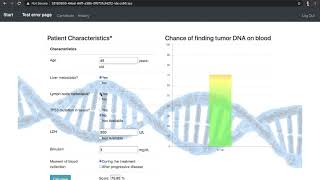

Predictive Score for Liquid Biopsy by Allan Andresson Lima Pereira

Using real data, I have created a score to predict the chance of detecting cancer DNA on blood, what would make a risky biopsy unnecessary. To make my score useful in clinical practice, I have developed a web application to both easily use it (using java script for graphical illustration) and also, add more data to further improve the performance of the method (using SQL).